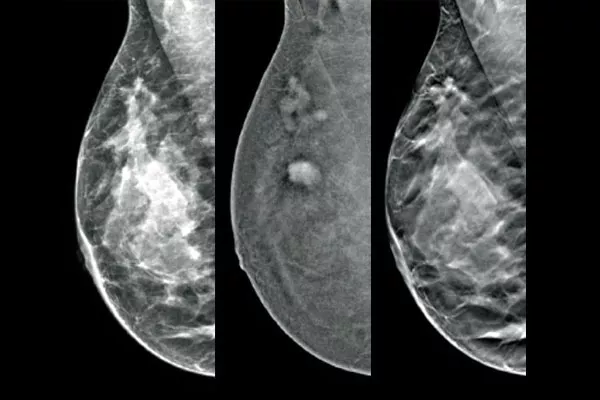

Targeting und Biopsie von Läsionen, die mit der kontrastverstärkten 2D-Mammografie erkannt wurden, anhand eines stereotaktischen Verfahrens mit vergleichbarer diagnostischer Leistung wie die Brust-MRT.1,2 Vergleich von Bildern nach Markierung in derselben Modalität in der die diagnostische Erstuntersuchung mit Kontrastmittel durchgeführt wurde.

Die Affirm Software für die kontrastverstärkte Biopsie ermöglicht die Durchführung einer Biopsie an Läsionen, die bei der I-View™ kontrastverstärkten 2D-Mammografie identifiziert wurden. Durch die Fähigkeit, kontrastverstärkte 2D- und Tomosynthese-Aufnahmen unter einer Kompression zu erstellen, ermöglicht das4 Affirm Steuerungssystem für aufrechte Brustbiopsien einen zügigen Übergang von der Früherkennung zur Biopsie. Dabei wird dieselbe bewährte Bildgebungskette5 wie beim Mammografiesystem genutzt, um die 3D™ Visualisierung verdächtiger Läsionen zu verbessern.

Eine effiziente und kosteneffektive Alternative zur MRT

Die funktionelle Bildgebung unter Verwendung von CEM bietet gegenüber der Brust MRT dank ähnlicher Sensitivität, höherer Spezifität und eines höheren positiven Vorhersagewerts Vorteile.7,8 Zusätzlich dazu stellt die CEM im Vergleich zur MRT aufgrund der kürzeren Verfahrensdauer7,10 eine kosteneffektive Alternative für die diagnostische Bildgebung dar.9